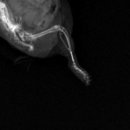

• 여울동물병원 | 용인 동물병원 강아지 십자인대 파열 수술 후기

용인 동물병원 강아지 십자인대 파열 수술 후기 ​ “갑자기 뒷다리를 못 딛고 들고 다니는데, 며칠 쉬면 괜찮아질지 수술까지 해야 하는 건지 고민됩니다.” ​ 이런 상황에서 내원하는 보호자들이 많습니다. ​ 강아지의 절뚝거림은 흔해 보이지만, 그 원인이 강아지 십자인대 파열 수술이 필요한 상태일 수 있기 때문입니다...